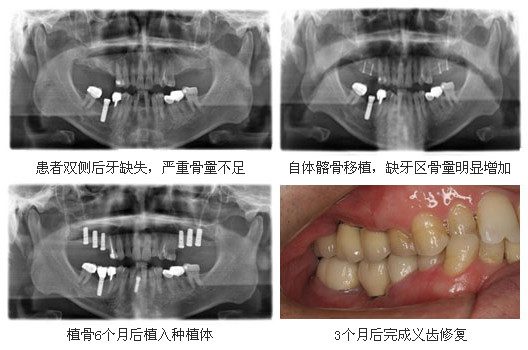

:各种牙列缺损,全口牙列缺失的种植治疗,各类复杂骨量不足的种植治疗,包括上颌窦底提升术,Onlay植骨,种植体倾斜植入技术等。在国内率先报道并开展超声骨刀在上颌窦底内提升术中的应用、小开窗术在上颌窦底外提升术的应用、种植义齿牙冠高度与咬合力关系的研究。